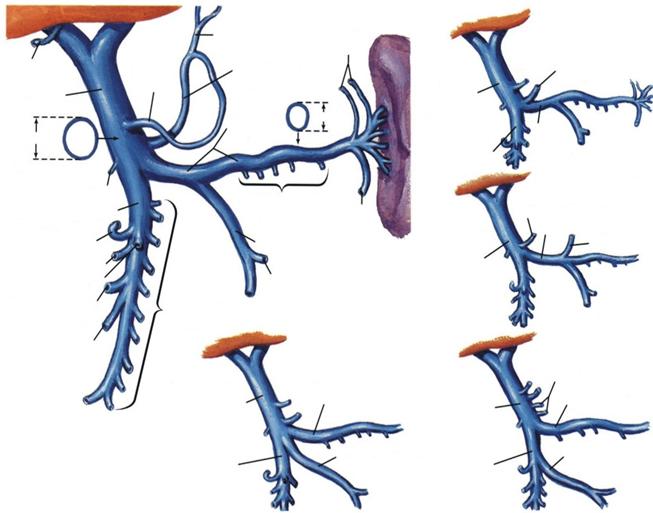

vena porta hepatica situata vena porta se poate deschide vena pulmonara se poate strictura congenitala a

anterior de capul pancreasului in VCI (arterele hepatice deschide in vena porta venei porte hepatice

si prima parte a duodenului apar marite) hepatica

v.esofagiana

v.cistica v.gastrica v.gastrica stanga v.gastrica stanga

dreapta

vena porta vena porta

0,45 cm

vena

E

1,09 cm splenica

VMI

v.gastroepiploica stanga v.splenica

v.gastroepipl.dr. VMI v.gastrica stg

vena porta

v.pancr-duod inf.

D

v.colica medie v.colica stanga

v.colica dreapta vv.jejunale

si ileale

v.ileocolica

vv.intestinale inalte

A

vena porta v.lienala vena porta v.splenica

A = dispozitie tipica (45%)

B = VMI se varsa in unghiul format de

varsarea VMS in v. lienala (30%)

C = VMI se deschide in VMS (25%)

D = v. gastrica stanga se varsa in

v. lienala (24% din cazuri)

E = v. gastrica stanga se varsa in un-

ghiul format de VMS si v. lienala

VMS

VMI VMI

B C

VARIANTE ALE VENEI PORTE